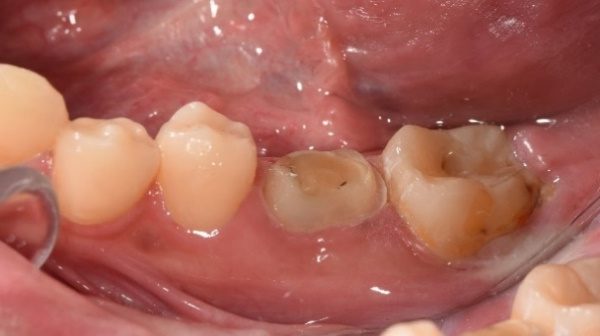

病患因牙根尖發炎,非常疼痛。由於該顆跟尖發炎牙齒從前已做過根管治療,無法再繼續使用,只能拔除。 經醫師評估後,該病患可以做自體牙移植手術,將口內有一顆無作用的智齒移植過來補這個位置。

治療前:牙根尖發炎

1.將上排智齒拔出

2.將智齒植入大臼齒位置,用鐵線固定